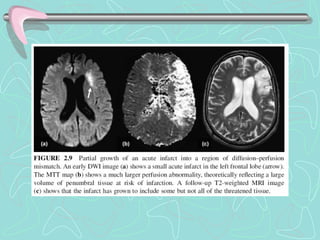

PENUMBRA ISQUEMICA

Core and penumbra in acute stroke imaging.

The infarct core, presumptively identified by an abnormality in a DWI image, represents tissue that

cannot be salvaged.

The ischemic penumbra represents tissue that is threatened by ischemia, but may still be saved by

timely therapy. The penumbra is presumptively identified as that tissue that is normal in early DWI

images, but abnormal in maps of CBF.

(a) Early DWI image shows several small closely clustered acute infarcts in the left corona radiata. An MTT map

(b) shows a much larger region of impaired perfusion, theoretically representing tissue at risk. However, a follow-up

T2-weighted FLAIR image

(c) shows that the infarct has not grown substantially.

Preservation of penumbral tissue, as demonstrated by this case,

… is the goal of acute stroke therapy.